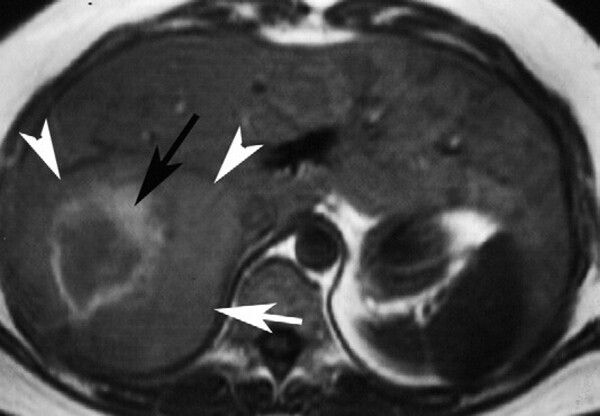

Hình 5. Hemangioma khổng lồ. Tổn thương giảm tín hiệu (mũi tên) trên hình T1W 3D GRE (A) và tăng tín hiệu (mũ I tên) kèm vùng nang ở trung tâm (đầu mũi tên) trên hình T2W SSFSE (B). Có bắt quang dạng nốt ngoại vi không kề nhau (mũi tên) ở thì ộng mạch (C), sau đó khuynh hướng lấp vào trung tâm hợp lưu (mũi tên) ở thì tĩnh mạch cửa (D). Tu y nhiên, không lấp đầy thuốc tương phản hoàn toàn (mũi tên ) ở thì muộn hình axial (E) và coronal (F).

FNH thường gặp nhất ở phụ nữ trẻ. Nguơi2 ta nghĩ rằng FNH là tổn thương hamartoma do dạng phát triển mất tổ chức hóa của tế bào gan và các ống mật hình thành một khối không có vỏ bao với ống mật và mạch máu có cấu trúc bất thường. Đặc điểm đặc trưng của FNH là hình thành sẹo xơ-mạch ở trung tâm. FNH thường nằm gân bề ặt gan. FNH có echo kém trên siêu âm. CT cản quang thấy bắt quang mạnh thì động mạch và tổn thương trở nên đồng đậm độ với nhu mô gan và khó phát hiện ở thì tĩnh mạch cửa. Sẹo trung tâm thường ít bắt quang ở thì động mạch sau đó bắt quang dần ở thì tĩnh mạch cửa và thì muộn (Hình 6).